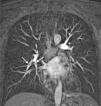

She was admitted to the Intensive Care Unit with the following test results: D-dimer positive, overloaded right ventricle on electrocardiogram and cardiac enzymes negative. Pulmonary thromboembolism was confirmed by angiotomography (Fig. 2). In two days, she presented elevation of muscle enzymes (CPK 10574 U/L and myoglobin 2563ng/ml), acute renal failure and sepsis secondary to limb ischaemia, owing to which she was subjected to supracondylar amputation due to the progressive systemic repercussion of the limb's ischaemia.